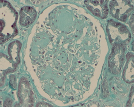

Patologia Molecular

A Patologia Molecular é a área da Anatomia Patológica que se debruça sobre a caracterização das doenças para lá do visível ao microscópio e à escala molecular.

No SAP-CHLO dispomos de técnicas de imunohistoquímica, hibridização in situ e PCR em tempo real, esta última aplicável em tumores sólidos e sangue periférico (biópsia líquida). Estas técnicas permitem a pesquisa de mutações genéticas no cancro, identificando aqueles que são susceptíveis de serem alvo de terapêuticas personalizadas, levando a melhores resultados terapêuticos e maior qualidade de vida para os doentes.